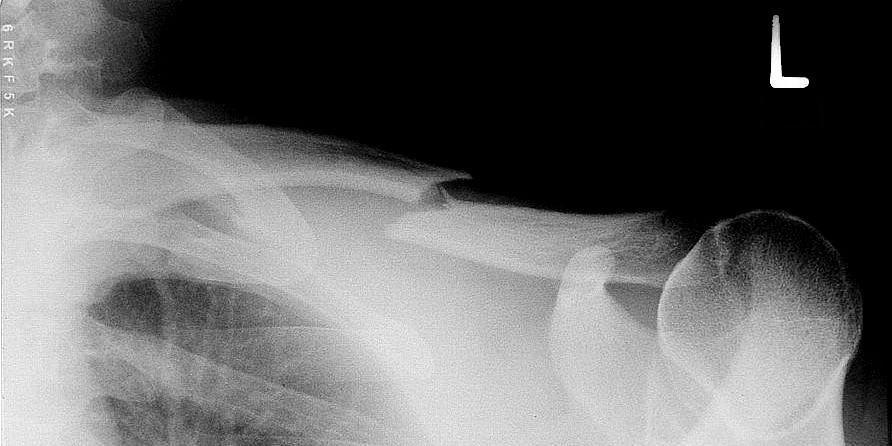

CC BY-SA 3.0, Link

- Fracture du ¼ externe (en fonction des ligaments coraco-claviculaires : classification de Neer)

- déplacements importants : raccourcissement > 2cm, translation >100% de la largeur de l’os.